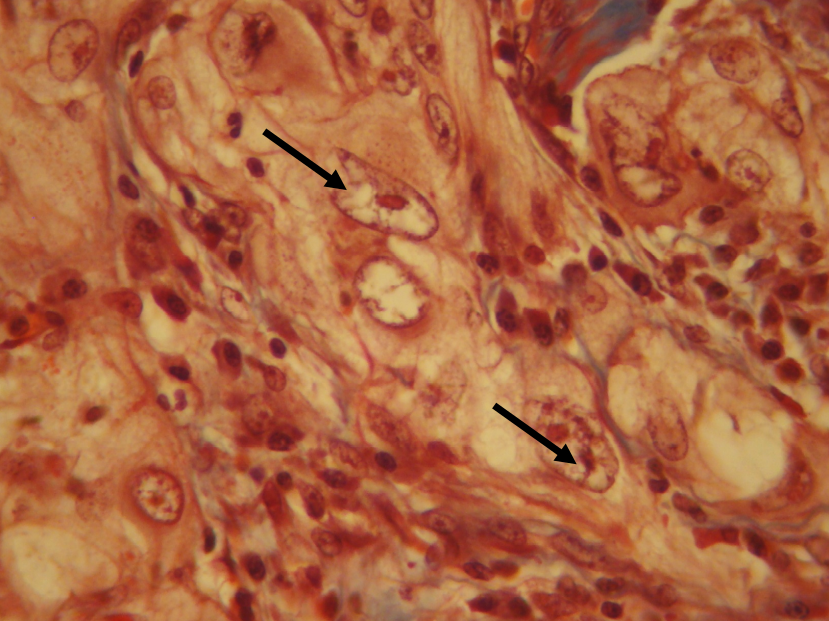

Carcinoma mucoepidermoide de bajo grado de malignidad. Estructuras quísticas revestidas por mucocitos (flecha). Tricrómico de Dane

Carcinoma mucoepidermoide de bajo grado de malignidad. Mucocitos (flecha blanca) y células epidermoides (flecha negra). Congestión vascular (flecha fina). Tricrómico de Dane